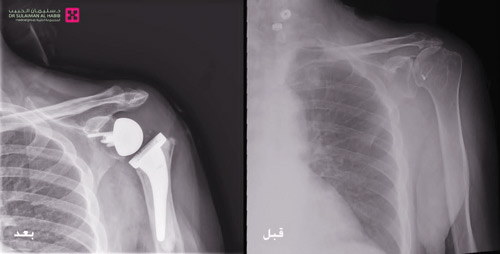

وأشار رئيس الفريق الطبي إلى أنه بعد دراسة نتائج الفحوصات والتاريخ المرضي، تم اتخاذ القرار بإجراء عملية جراحية لزراعة مفصل صناعي «معكوس» للكتف ، موضحاً أن هذه العملية استغرقت 5 ساعات وهي الأولى من نوعها بمنطقة القصيم وتعد من الجراحات المعقدة، وتم فيها تنظيف محيط المفصل القديم من التكلسات والزوائد العظمية المسببة للاحتكاكات، ومن ثم تركيب المفصل الصناعي الجديد المصنوع من مادة الكوبلات والكروم، والذي يتميز بجودته العالية ويساعد في تحقيق المرونة الكاملة للمفصل ومجال أكبر من الحركة والأريحية.

وقال رئيس الفريق الطبي بالمستشفى إن الجهود المبذولة تكللت بالنجاح ولله الحمد، وتم نقل المريض بعد الجراحة إلى جناح التنويم. وبعد ذلك تم البدء في تطبيق برنامج العلاج الطبيعي المكثف ، ومن ثم عاد المريض إلى منزلة بعد 5 أيام وهو بصحة جيدة ، وقد انتهت لديه الآلام السابق ذكرها ، وبدأ يمارس حياته بصورة طبيعية بعد أن استعاد كامل مرونة وحركة المفصل.